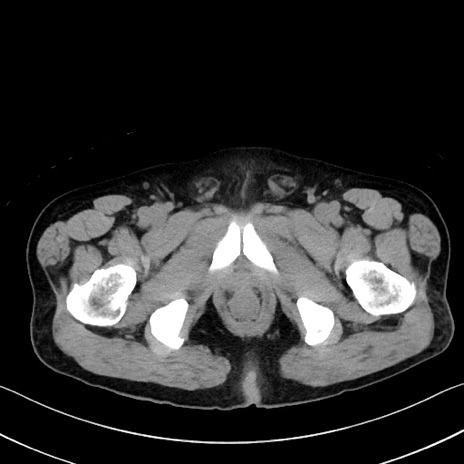

症例35(横断像)

【症例】70歳代 男性

【主訴】腹部膨満、嘔吐

【現病歴】昨日より腹部膨満感出現。本日増悪し、仙痛出現。嘔吐あり、受診。

【既往歴】糖尿病、胆摘後

【身体所見】BP 149/80mmHg、HR 74/min、BT 35.9℃、腹部:膨満、軟、圧痛なし。腸雑音減弱あり。上腹部正中切開瘢痕あり。

【データ】WBC 13500、CRP 1.72